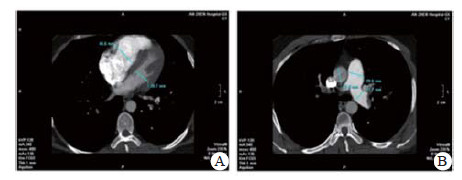

实验室检查结果:动脉血气分析pH 7.458, PaO2 60.5 mmHg, PaCO2 26.7 mmHg, SpO2 92.0%;D-二聚体2 655 ng/mL; BNP 163.00 pg/mL; 血常规WBC 5.91 ×1012/L, NE 73.8%, HGB 138.0 g/L, PLT 286 g/L; 同型半胱氨酸(HCY)14.0 μmol/L (正常值:6~14 μmol/L); 纤维蛋白原定量(FBG) 0.520 g/L(正常值:2.000~4.000 g/L), 纤溶酶原活性39.0%(73.0%~127.0%), 纤溶酶原抑制物-1(PAI-1)6.898 ng/mL(正常均数4.207 ng/mL), 组织纤溶酶原激活物(t-PA) 5.135 μg/L(正常均数2.375 μg/L); 血浆抗凝血酶Ⅲ(AT-Ⅲ:A)、血浆蛋白C活性(PC:a)、血浆蛋白S活性(PS:a)以及狼疮抗凝剂(Lupus anticoagulant, LA)水平在正常范围内。行经胸壁超声心动图检查提示右心扩大(因肺动脉瓣及三尖瓣反流极少, 无法准确估测肺动脉压力), 肺动脉增强CT(pulmonary artery computed tomography angiography, CTPA)提示右室扩大、两肺动脉主干及分支可见多发充盈缺损(图 2)。下肢静脉多普勒超声提示右侧腘静脉急性深静脉血栓形成及右侧股浅静脉血栓形成, 左侧髂静脉及左下肢深静脉未见明显异常。诊断为急性PE(高危组)、KTS。评估后给予重组组织型纤溶酶原激活物(r-tPA)50 mg 2 h内静脉泵入溶栓治疗, 溶栓过程中(r-tPA使用至35 mg时)患者出现咯血约200 mL, 遂被迫停止溶栓治疗, 监测活化凝血时间(accelerated clotting time, ACT)降至200s时给予普通肝素持续泵入并维持ACT于180~220 s, 肝素抗凝治疗48 h后改为低分子肝素(low molecular weight heparin, LMWH)联合华法林治疗, 期间未再发生咯血症状。入院第4天完善肺通气/灌注显像检查, 并提示:左肺下叶, 右肺中叶内段(亚段)、中叶外段、下叶前基底段、外基底段、后基底段血流灌注可见放射性分布稀疏缺损区, 双肺多发PE(累及8个肺段及1个亚肺段), 肺血流灌注受损范围占双肺容积的51%;入院10 d后复查CTPA, 结果显示两肺动脉主干腔内充盈缺损完全消失(图 3)。住院治疗15 d患者好转出院, 院外口服华法林抗凝治疗, 定期监测国际标准化比值(INR), 且维持于PE治疗范围2~3之间。抗凝治疗1年后进行肺通气/灌注显像复查, 提示右肺下叶前基底段、外基底段血流灌注改善, 左肺下叶, 右肺中叶内侧(亚段)、中叶外段、下叶后基底段血流灌注恢复正常。随访3年以来, 患者院外规律服用华法林抗凝治疗, 定期监测INR, 定期复查超声心动图及肺通气/灌注显像检查, 出院3个月超声心动图检查肺动脉压力正常、三尖瓣反流消失; 出院12个月及33个月复查肺通气/灌注未见新发的血流灌注稀疏缺损区, 出院33个月复查双髂双下肢静脉超声未见明显阻塞, 随访期间未出现出血或其他不良事件, 出院1个月后恢复工作至今, 一般状况良好。

| 图 2 患者CTPA(溶栓前):房室瓣水平显示右室明显扩张(A); 主肺动脉水平显示肺动脉增宽(B) |

| 图 3 患者溶栓后10 d复查CTPA, 右室扩张明显好转(A)、肺动脉增宽有所缓解(B) |